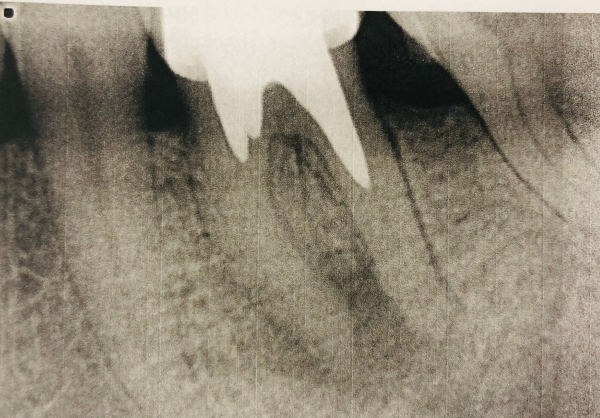

У меня установлена единственная вкладка, корня нет. Вкладку установили пять лет назад, все было нормально. Месяц назад заныло, и вздулся флюс, при этом десна не воспалилась и не покраснела, не болело, а ныло неприятно. Пропила антибиотик неделю и проводила полоскание йод-соль-сода. К стоматологу попаду не скоро, но снимок сделала.

Прикрепленые фото

Зуб необходимо перелечить в ближайшее время, необходимо купировать воспалительный процесс. Для этого удаляется вкладка, проводится ревизия корневых каналов, после изготавливают новую вкладку и покрывают коронкой зуб в случае необходимости.